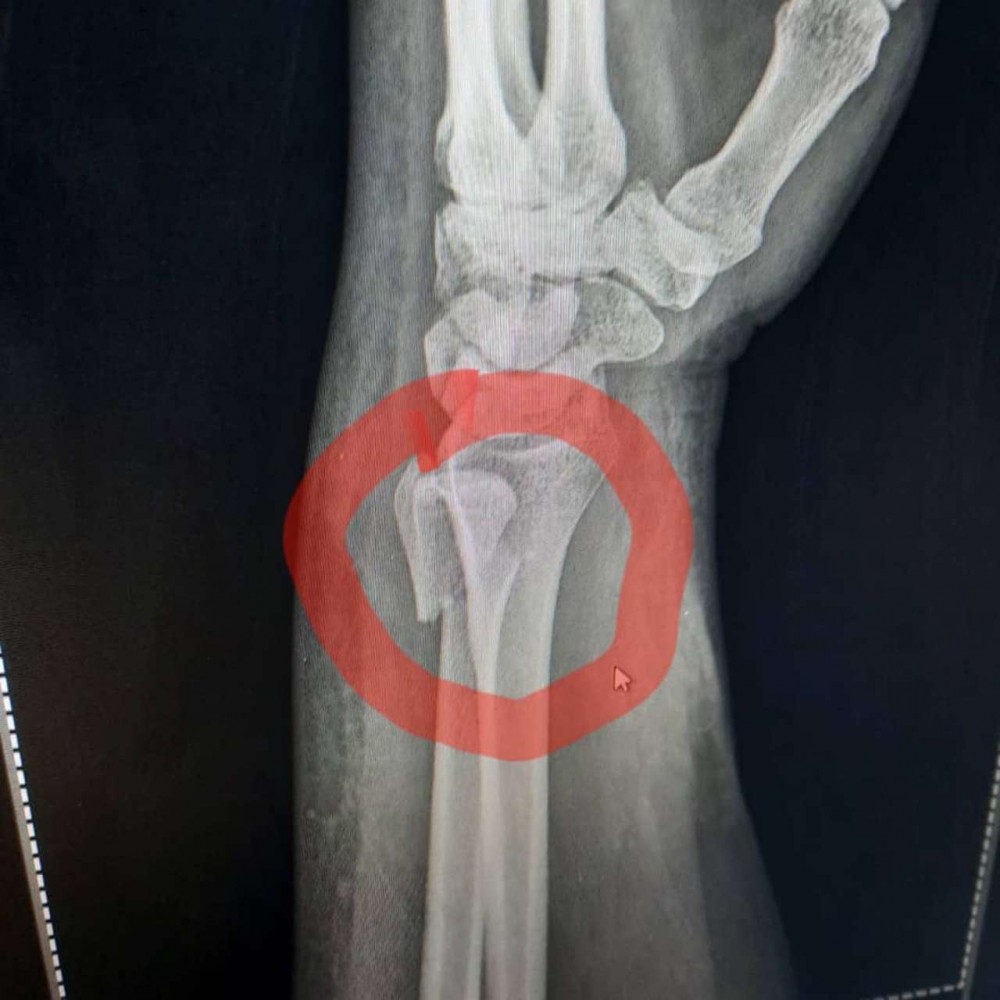

Azərbaycanlı aparıcının biləyi qırıldı - FOTOLAR

Tanınmış aparıcı Aytən Səfərovanın başına iş gəlib.

32gun.az xəbər verir ki, aparıcının bilək sümüyü sınıb. Bu barədə Səfərova instaqramda məlumat yayıb. O bildirib ki, bu günlərdə anası ağır əməliyyata hazırlaşır:

“Çox çalışdım ki, könlümü fərəh tutum, fikirləşdiyimi büruzə verməyim, özümü “sındırmayım”, lakin sümüyümü sındırdım. Həkimlər vaxtında müdaxilə etdilər.  Hələ ki, ağrıkəsicisiz mümkün deyil, amma biz güclü qadınıq. İnşallah bu da keçər. Özünüzü qoruyun”.